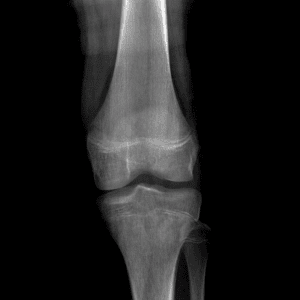

Pediatric Radiographs